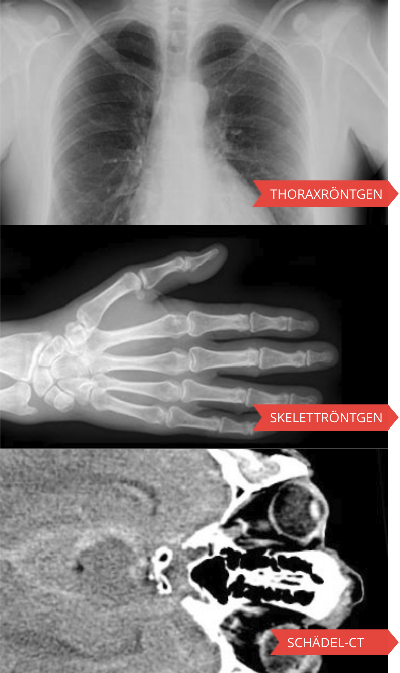

Radiosurf

Pedirad